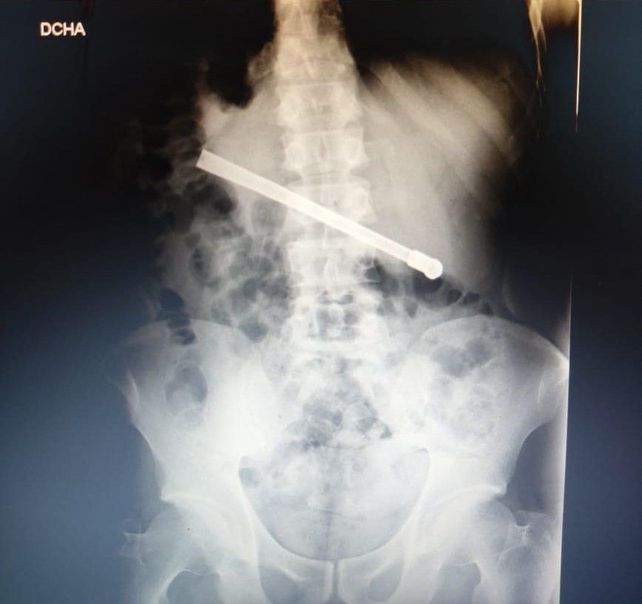

La radiografía mostró que tenía una bombilla

Un preso que se encuentra alojado en el Complejo Penitenciario Rosario (CPR) se tragó una bombilla de mate y tuvo que ser operado en el hospital Eva Perón. El hombre, de 35 años, tenía el objeto atravesado en el tórax y fue intervenido quirúrgicamente este martes.

Al continuar con el malestar, le realizaron una placa radiográfica en la Unidad Penitenciaria ubicada en 27 de Febrero al 7800, y pudieron determinar que había ingerido una bombilla de mate que quedó alojada transversalmente en la cavidad torácica.